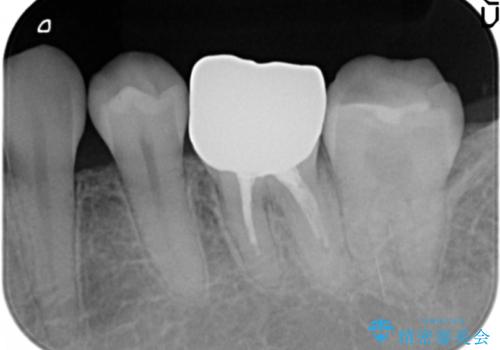

- 笑った時に目立つ、下の歯の銀歯をセラミックにしたいと来院されました。

症状・病変はなかったため根管治療は行わず、クラウンのやりかえのみの治療計画としました。